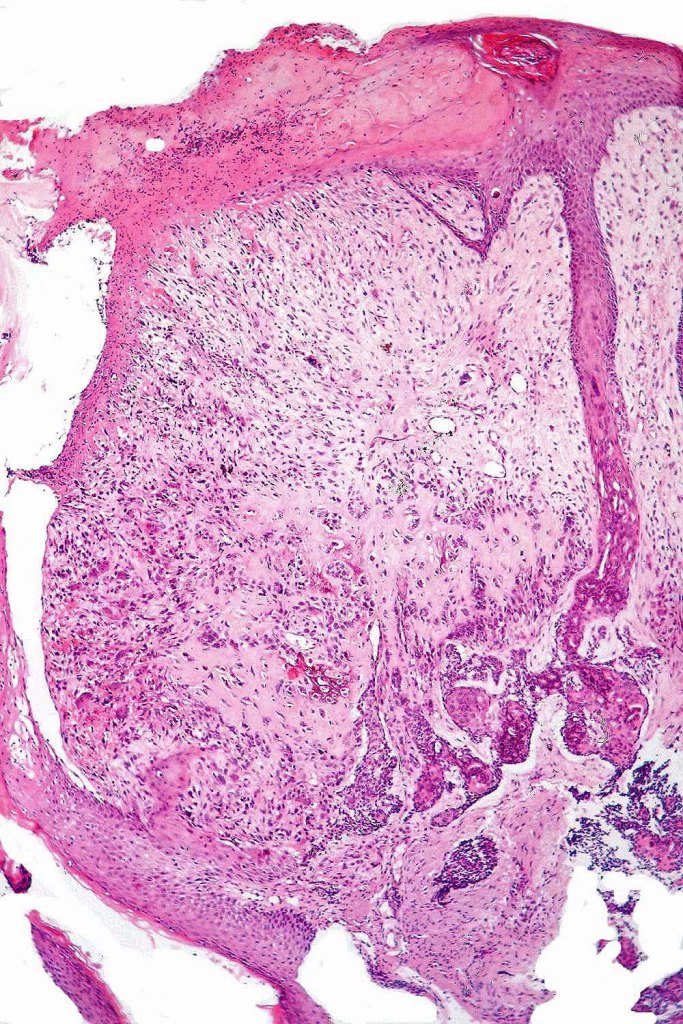

Carcinosarcoma

Cutaneous carcinosarcoma (metaplastic carcinoma, carcinoma with heterologous differentiation)

Histological features

•Osteoid

•Chondroid

•Smooth muscle

•MFH-like features with osteoclasts

•Neural differentiation